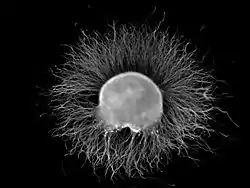

Ganglion

A ganglion (pl.: ganglia) is a group of neuron cell bodies in the peripheral nervous system. In the somatic nervous system, this includes dorsal root ganglia and trigeminal ganglia among a few others. In the autonomic nervous system, there are both sympathetic and parasympathetic ganglia which contain the cell bodies of postganglionic sympathetic and parasympathetic neurons respectively.

Ganglia are primarily made up of somata and dendritic structures, which are bundled or connected. Ganglia often interconnect with other ganglia to form a complex system of ganglia known as a plexus. Ganglia provide relay points and intermediary connections between different neurological structures in the body, such as the peripheral and central nervous systems.